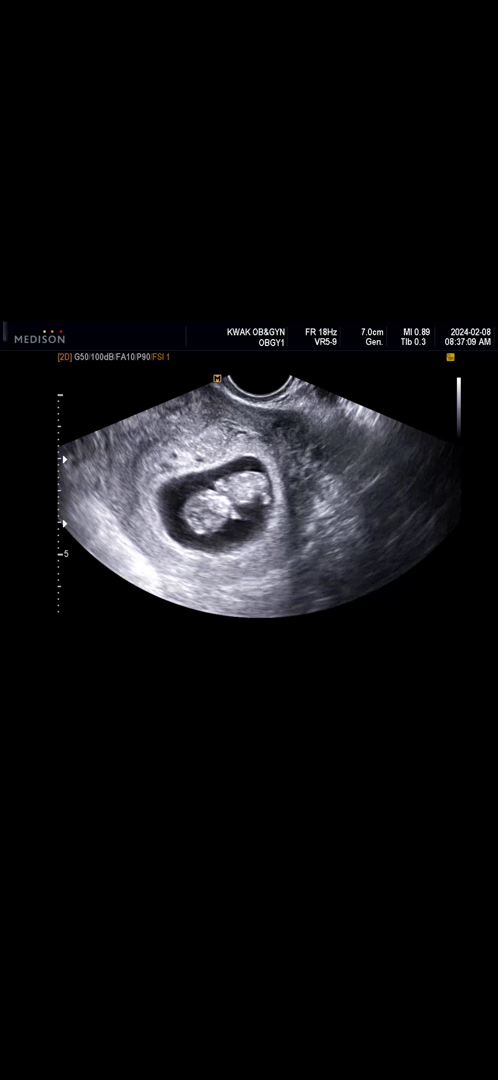

9주차 초반인데 아기집 이정도면 괜찮나요 ?

3일전 병원에서 복부초음파를 했을 때는 아기집이 좀 더 컸는데 배가 새벽에 너무 아파 병원에 가서 질 초음파로 봤는데 아기집이 저렇게 작아졌더라구요 … 아이는 0.3cm 컸구요~ 혹시 질 초음파로 봐서 아기집이 작아지게 보일 수도 있을까요 ~ ?